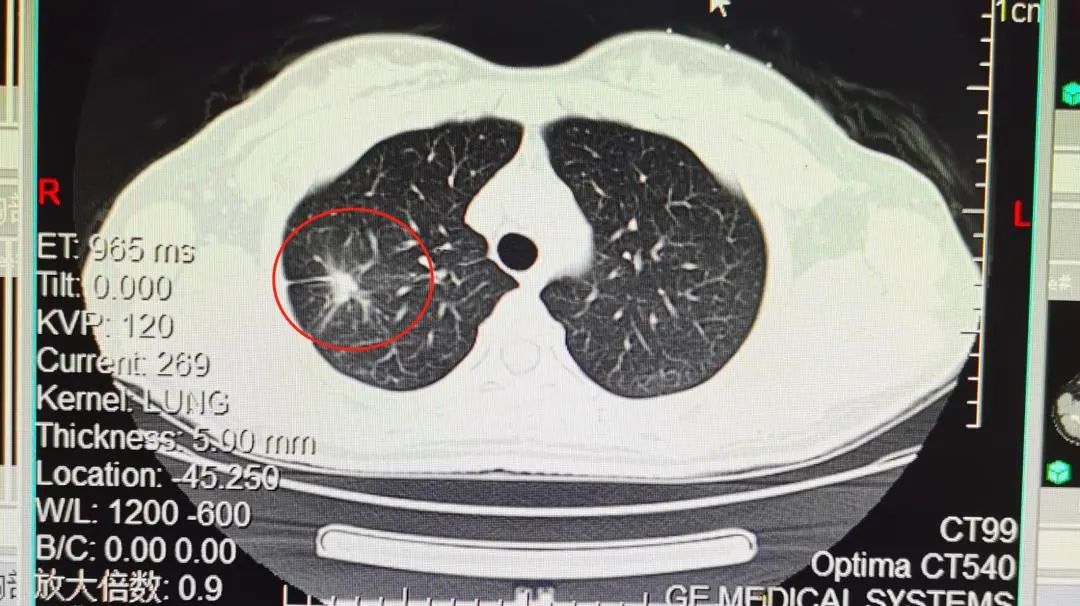

他比较紧张,选择手术切除,病例就是肺结核: 当然了,某些不典型病灶